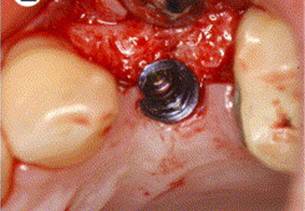

PLACEMENT OF DENTAL IMPALNT

PILOT DRILL

IMPLANT IN SITU

LABORATORY PROCEDURES

ABUTMENT PLACEMENT

PROSTHESIS